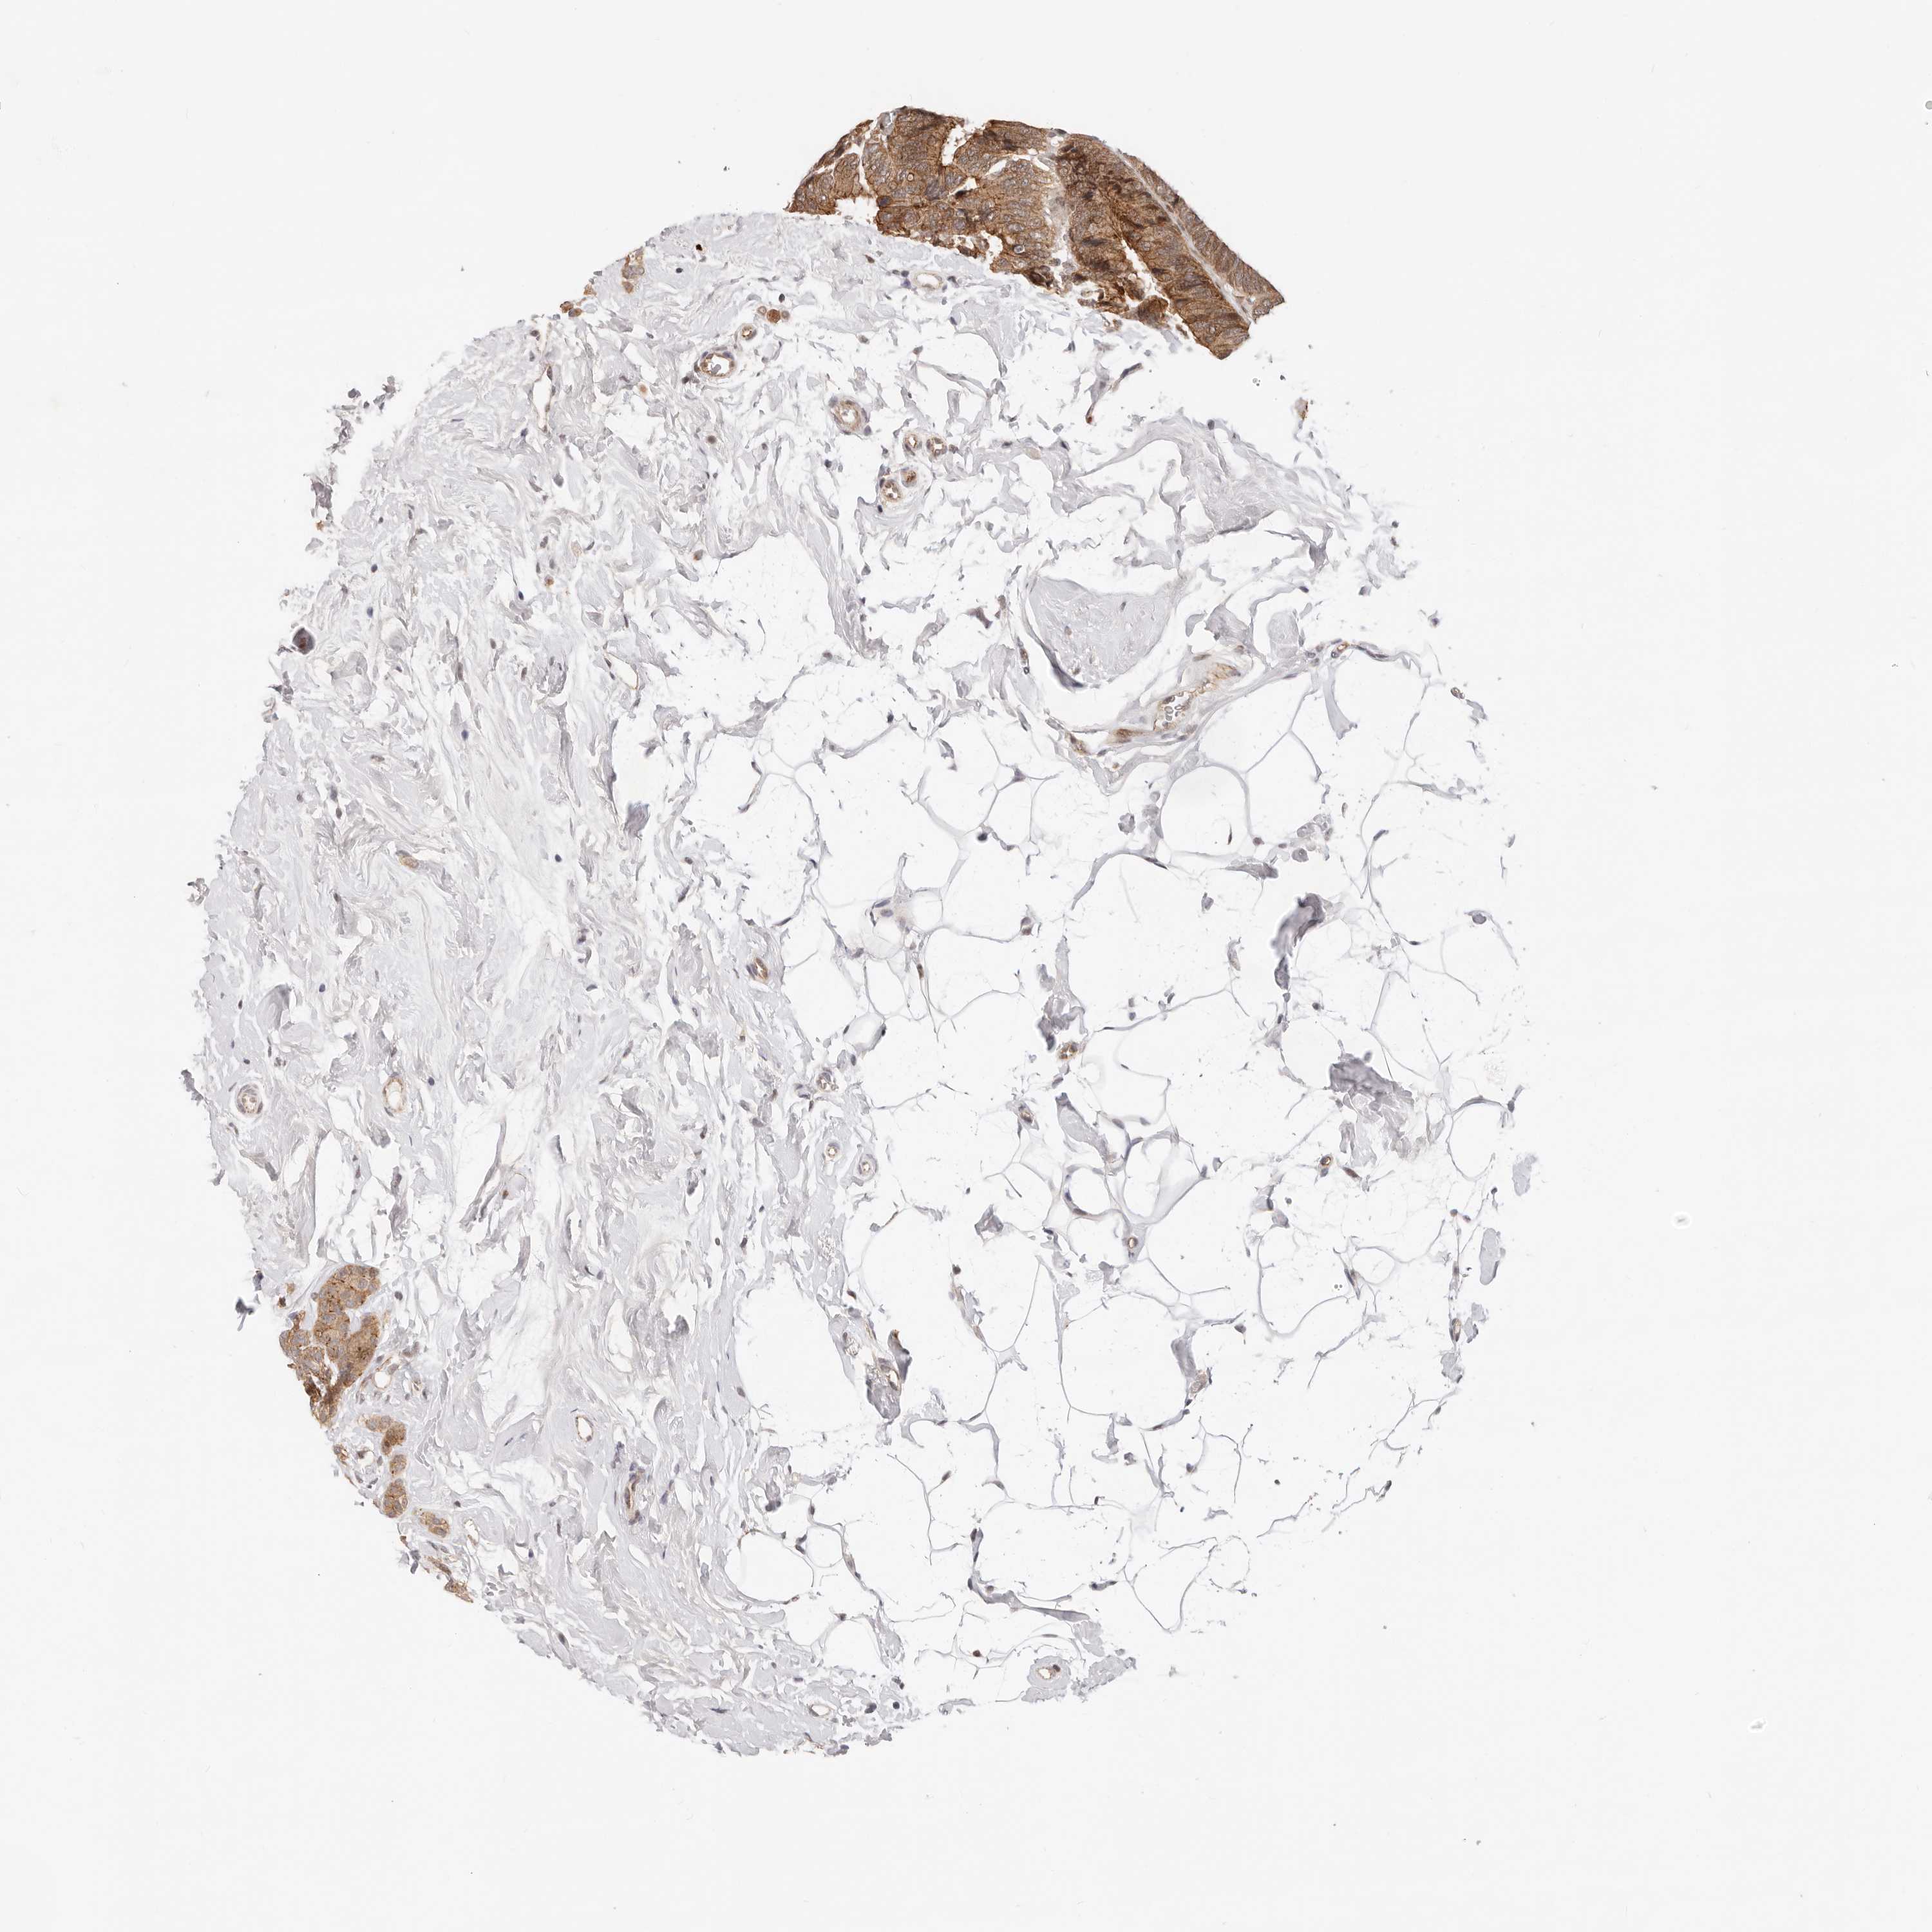

BRCA TCGA BRCA VALIDATION PROTEIN EXPRESSION

ANTIBODIES

AND

VALIDATION